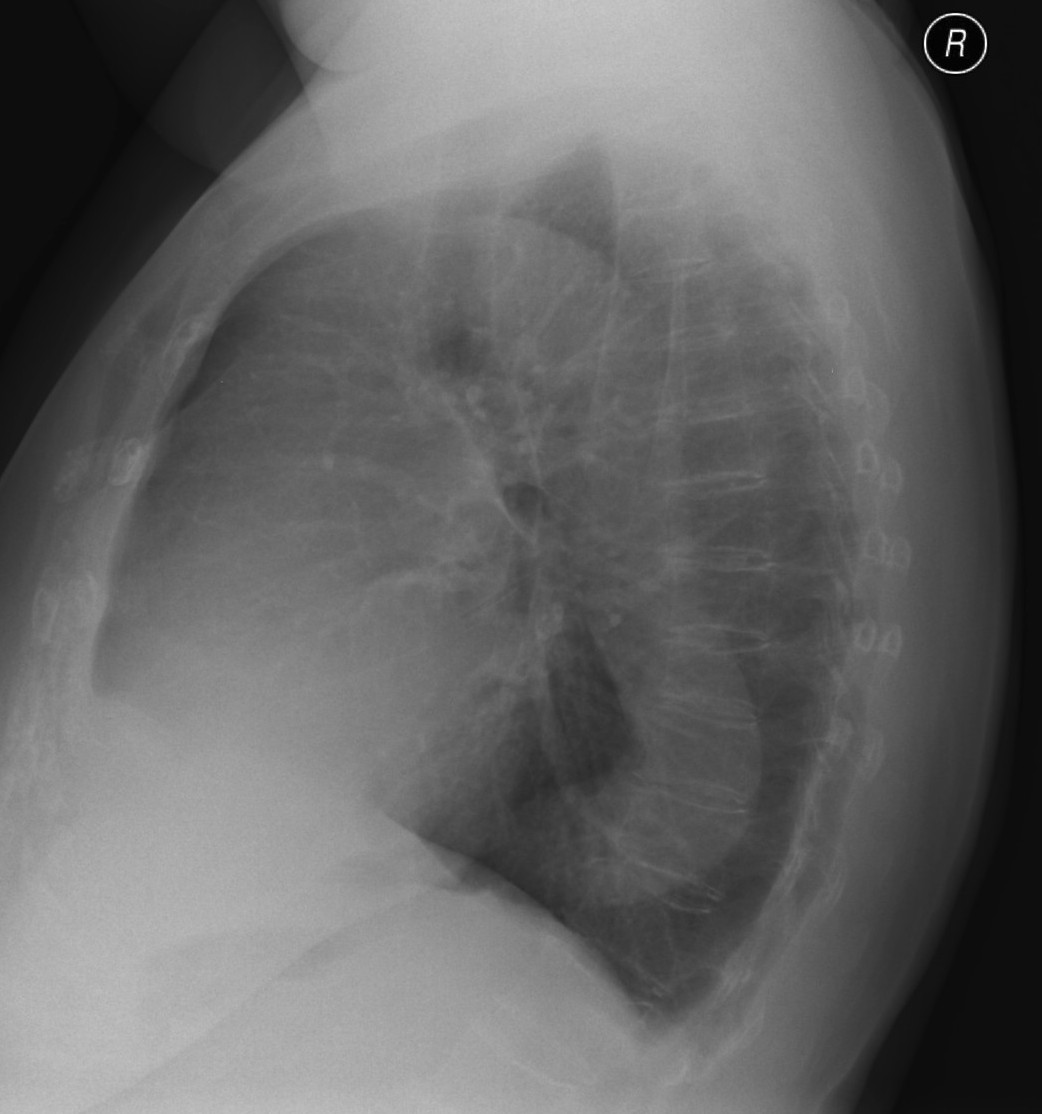

5a,b: Lung abscess. Chest radiograph, bidirectional (PA+lateral - right side near the film).

61 year old woman. Laparoscopic esophagus diverticulum resection 2 months ago. 7 cm air-fluid level with air space above: „basket sign” above the right diaphragm laterally measuring 2,5 cm in lateral diameter and 7 cm mediodorsally.